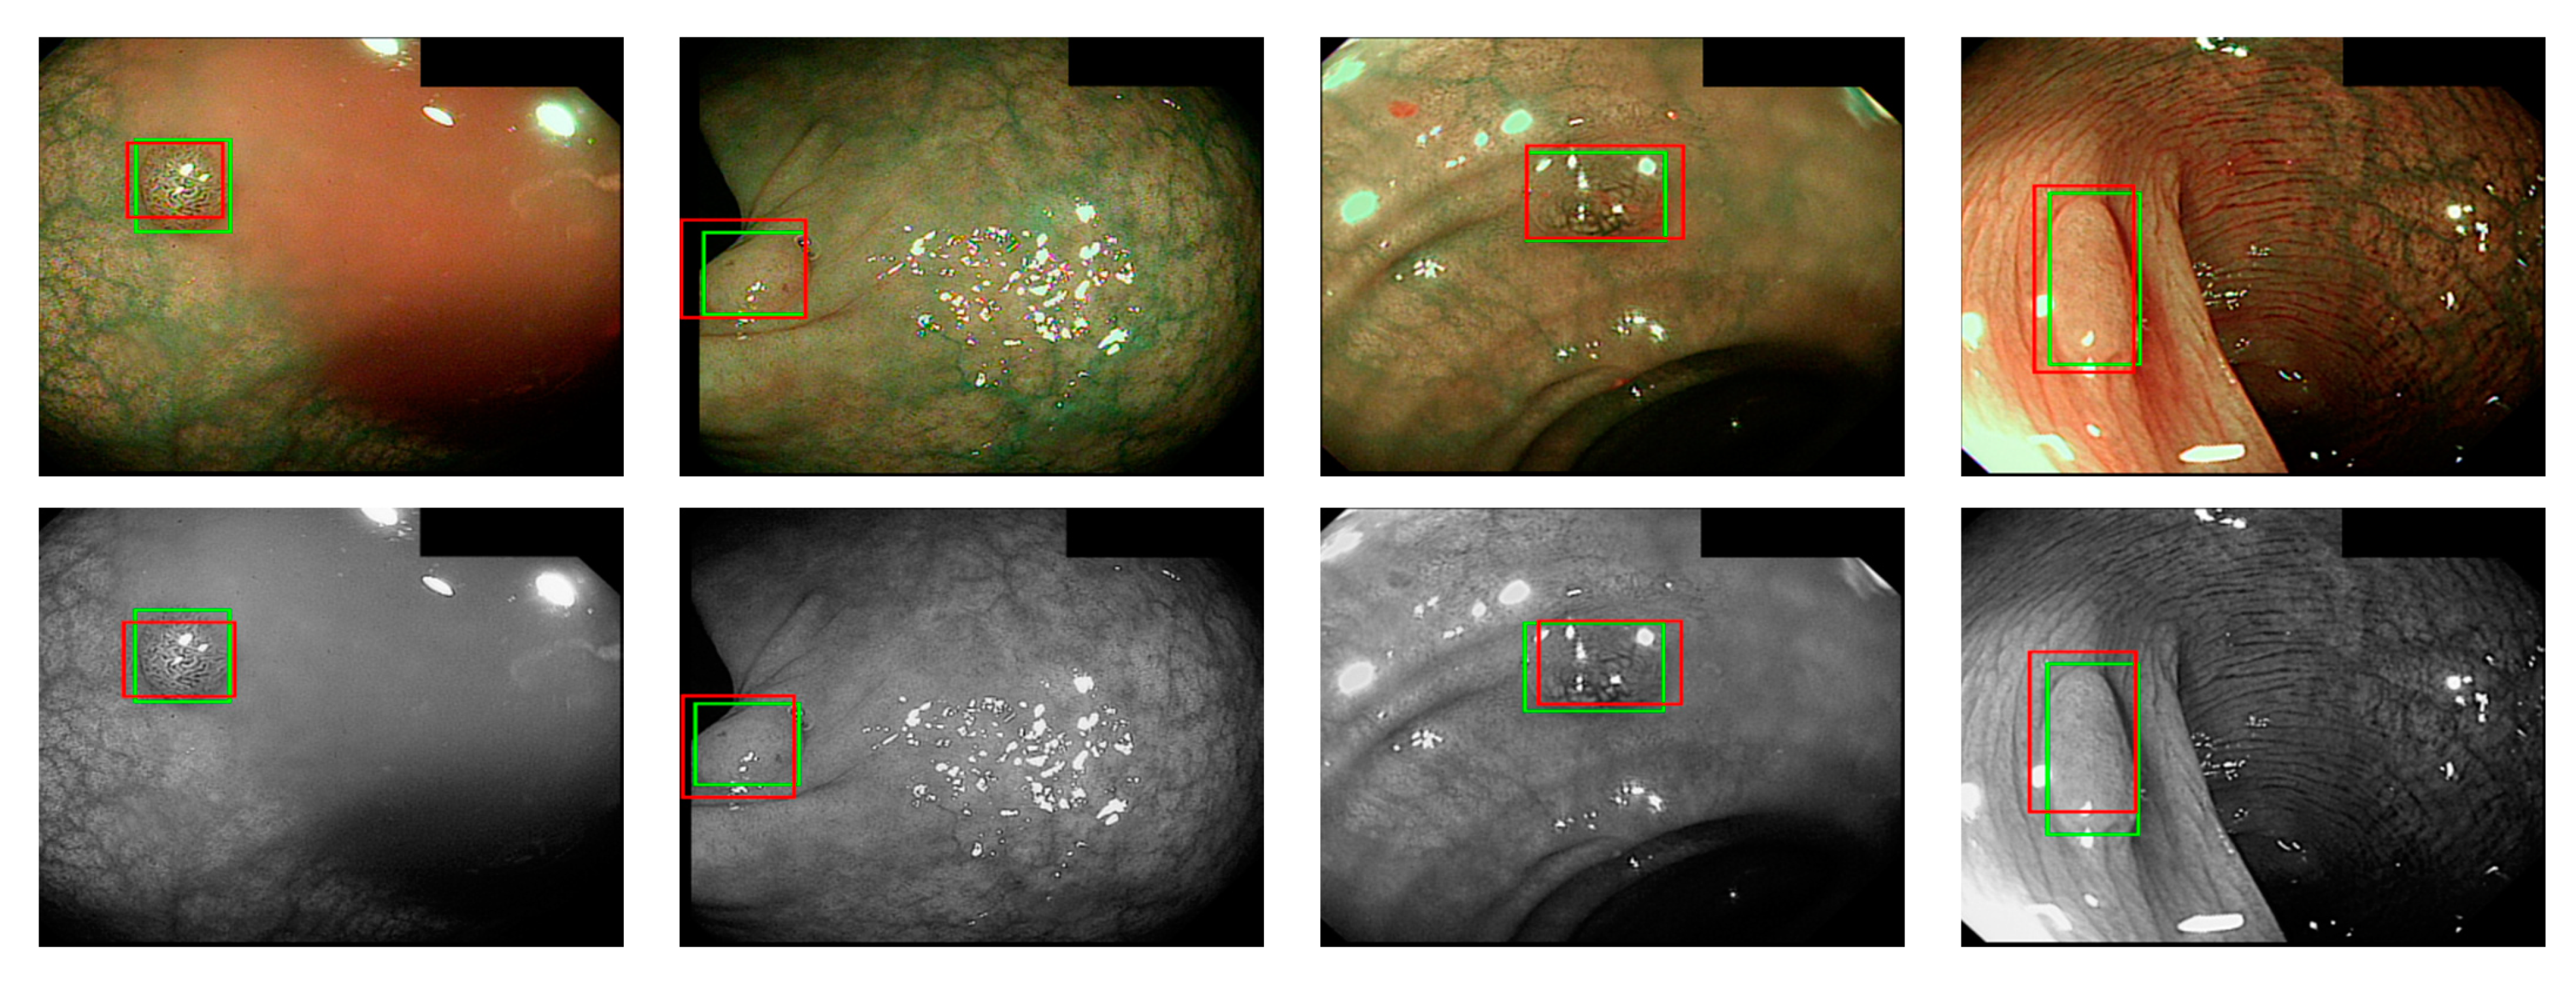

Figure 10.

WL polyp detection.

Figure 11.

NBI polyp detection.

where ai is the input value; p is the pooling regions; n is the pooling size; and aj is the output value after the maximum value is obtained. Polyp detection was then conducted in the bounding box transform layer. The prediction result of the feature map was obtained in the last layer and was output through a 1 × 1 convolutional layer by using a pixel-based approach and converted to a bounding box mode for display [50]. There are eight groups of bounding boxes to locate the polyps: (16, 16), (32, 32), (24, 48), (48, 24), (60, 80), (108, 72), (216, 144), and (180, 180). The cutoff value of polyp detection is 0.2. The size of the predicted bounding box was adjusted by converting it to the range of a true-value bounding box. Table 3 displays the framework of the CNN model. Figure 10 and Figure 11 show the results of WL and NBI polyp detection, respectively, where the first column is the RGB image; the second column is the grayscale image; the red box is the prediction box; and the green box is the actual polyp location marked by the clinician, namely the GT.